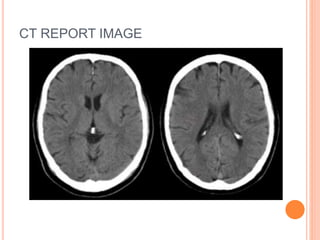

1. CT Scan (Computerized tomography)

CT REPORT IMAGE